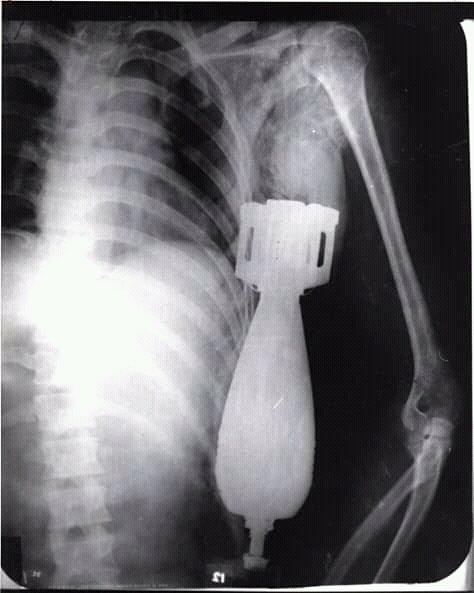

阮文龙的X光照

之后,阮文龙的战友谨慎翼翼地将他送到了岘港海军医院,美军军医哈利·丁斯摩尔(Dr.Harry Dinsmore)为其进行外科手术。由于这枚炮弹仍有爆炸的可能,因此哈利·丁斯摩尔疏散了医院的人群,并让其他士兵在手术室外用沙袋构筑了防爆工事。当一切处理妥当后,哈利·丁斯摩尔为阮文龙拍摄了X光图片,最终确定这枚炮弹没有卡在骨头上,也没有伤及阮文龙的脏器,随后哈利·丁斯摩尔决定立即对阮文龙展开外科手术。